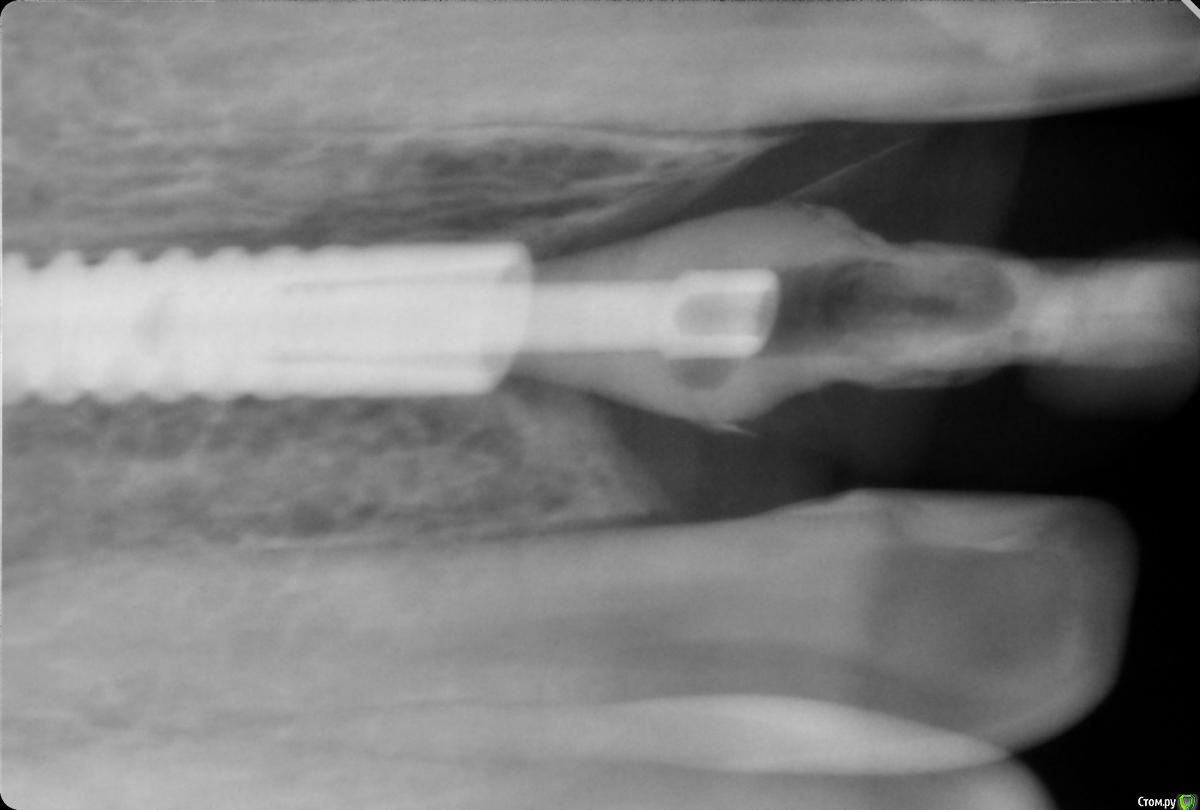

Оле Опубликовано 11 января, 2020 Поделиться Опубликовано 11 января, 2020 Здравствуйте! Коронка временная, осенью заметила подтекание гноя, пошла в клинику - снимок, сказали, что все ок, посоветовали заменить временную коронку на другую временную, так как эта уже стоит давно (прохожу лечение, пока не могу поставить постоянную).Пользуюсь ирригатором, перешла на насадку для промывания карманов, добавляю в воду ротокан.Гной продолжал выделяться. Снова пошла в клинику, к ортопеду, с просьбой заменить коронку. Ортопед сделала снимок и отказала - мол, зачем тратить деньги, коронка стабильна, стоит хорошо, имплант в порядке, ходите с этой. Мол, "не трогай лихо, пока оно тихо".Но гной продолжает выделяться. Цвет десны спокойный. Как поступить? Меня беспокоит и выделение, и запах. Может, я мнительная, и связи нет, но последние две недели болезненное состояние, горло и нос (выделения без заложенности), облегчилось антибиотиками после первой же таблетки, но симптомы не пропали (на них уже 6 дней) . Ссылка на комментарий

Оле Опубликовано 11 января, 2020 Автор Поделиться Опубликовано 11 января, 2020 Ортодонтия сейчас, прикус поднимают, выравнивают. и потом протезирование боковых уже надо. То есть с временным мне ещё год-полтора. Но столько времени с запахом и подтеканием... Это ужас.С костью действительно все в порядке? Поможет ли смена временной коронки? Постоянную док тоже отказался ставить, сказал, что до конца ортодонтии это потеря денег, прикус меняется, и нагрузка большая на этот зуб сейчас. Ссылка на комментарий